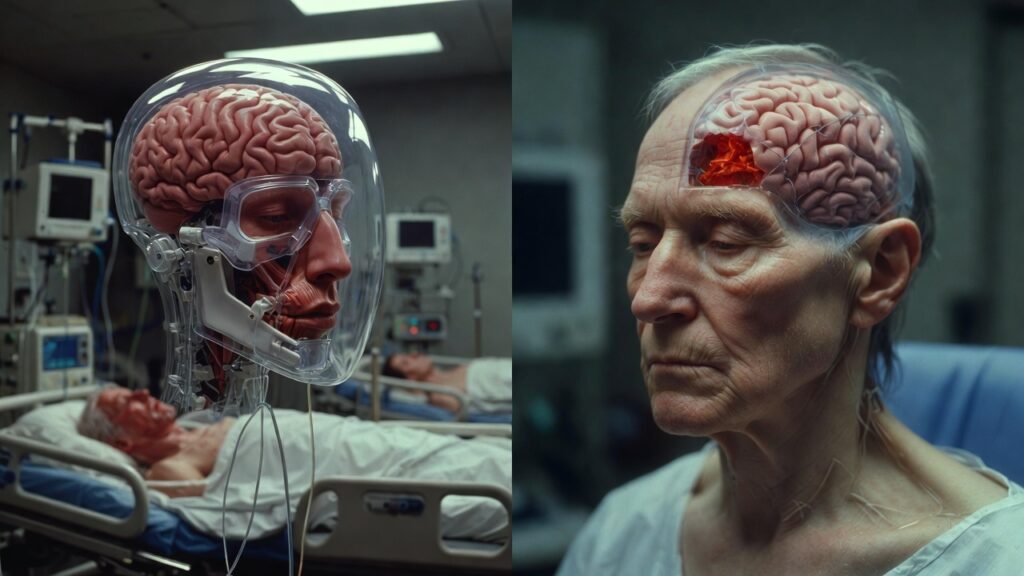

- Acute encephalitis

- Seizures

- Loss of consciousness

- Coma

Complications and Long-Term Consequences

High Mortality Rate

The nipah virus infection rate can range anywhere from 40% to 75%, depending on the outbreak and the healthcare infrastructure that is in place.

Neurological Sequelae in Survivors

Survivors may suffer from long-term complications, including:

- Persistent cognitive impairment

- Memory deficits

- Speech and motor difficulties

- Seizure disorders

- Chronic fatigue

Diagnosis of Nipah Virus

A high suspicion level and specialized laboratory facilities are required for diagnosis. Common diagnostic methods include:

• RT-PCR testing of blood, cerebrospinal fluid, urine, or throat swabs

• ELISA for antibody detection

Early diagnosis is critical but challenging, particularly in low-resource settings.

Supportive Care

- Management is largely supportive and includes:

- Intensive care monitoring

- Treatment with oxygen or mechanical ventilation

- Management of seizures

- Management of cerebral edema

- Strict isolation precautions